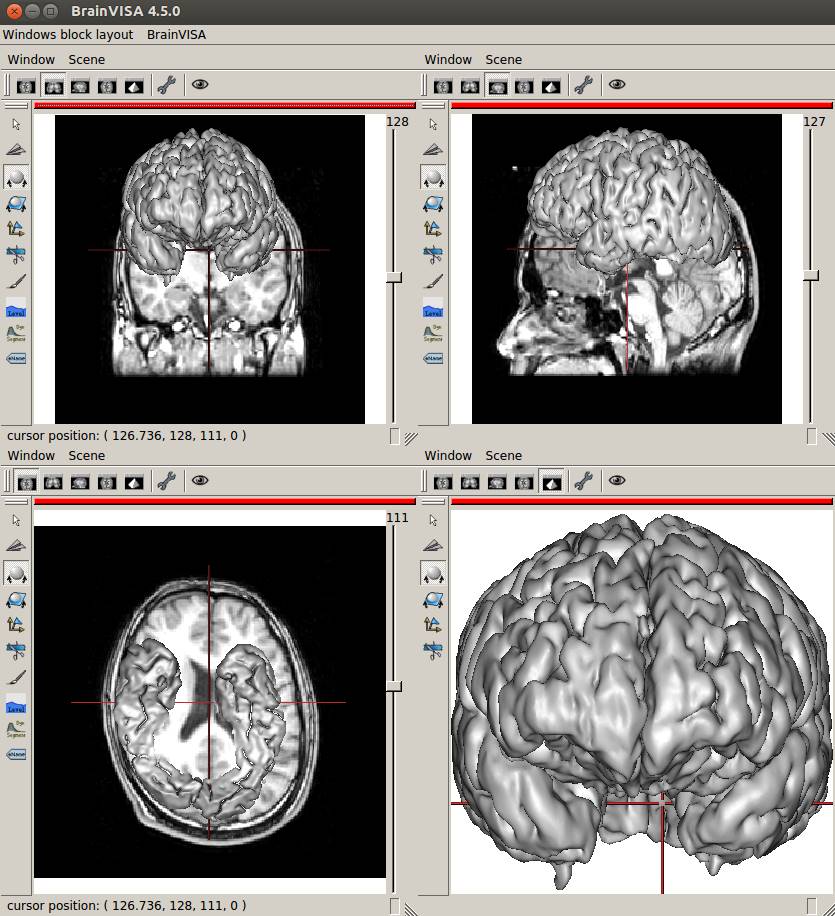

aseg.mgzをaseg.nii.gzに変換して四面Anatomistで見てみました。

残念ながらBrainVISAで作成した脳表メッシュとは座標が異なるようです。

四面Anatomistで元画像と一緒に表示してみます。

座標はあってません。